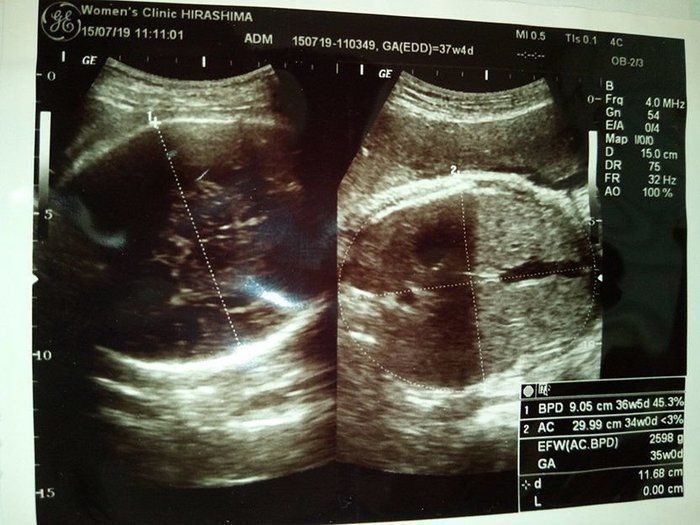

水野谷つむぎさんの妊娠37週目のエコー写真 赤ちゃんの推定体重2598g いつでも出ておいで!

出産するのは実家に近い病院だったこともあり、まだ自宅にいた私は通院回数が増えたことでしんどくなってきていました。でも、まだ里帰りをするのが嫌で自宅で粘っていました。自宅で産気づいたときの対策として、子育てタクシーの対応がある会社へ、今更ながら問い合わせをしました。